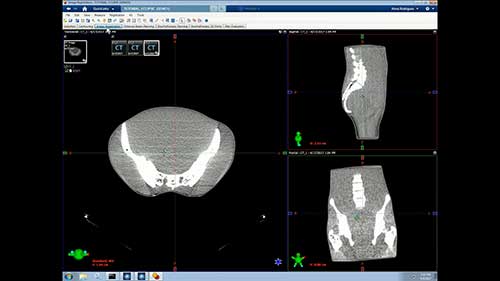

乳腺癌放射治疗——副作用

简介:乳腺癌患者需要了解放射治疗的短期副作用和长期副作用,以及如何对抗副作用,获得情感和心理支持。